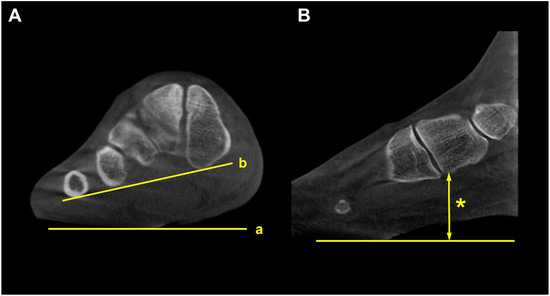

Forefoot arch angle (FAA) and medial cuneiform-to-floor distance (MCFD) are the measurements used to evaluate medial column instability in PCFD [36]. FFA is determined in the coronal plane by establishing a line from the most plantar aspect of the medial cuneiform to the fifth metatarsal. The angle between this line and the ground is defined as FAA. MCFD is measured in the sagittal plane from the most plantar aspect of the medial cuneiform to the ground plate (Figure 10). de Cessar Netto et al. reported that both FAA and MCFD reflect medial column instability with almost perfect reliability [36]. In non-weight-bearing and weight-bearing CT scans, the MCFD measured 29 mm and 18 mm, respectively, and the FFA measured 13 degrees and 3 degrees, respectively, indicating medial column instability with differences observed under weight-bearing conditions.

Figure 10.

Forefoot arch angle (FFA) and medial cuneiform-to-floor distance (MCFD). (A) FFA is defined as an angle between the floor (a) and the line connecting the most plantar aspect of the medial cuneiform and 5th metatarsal (b). (B) MCFD is measured from the most plantar aspect of the medial cuneiform to the floor (asterisk).